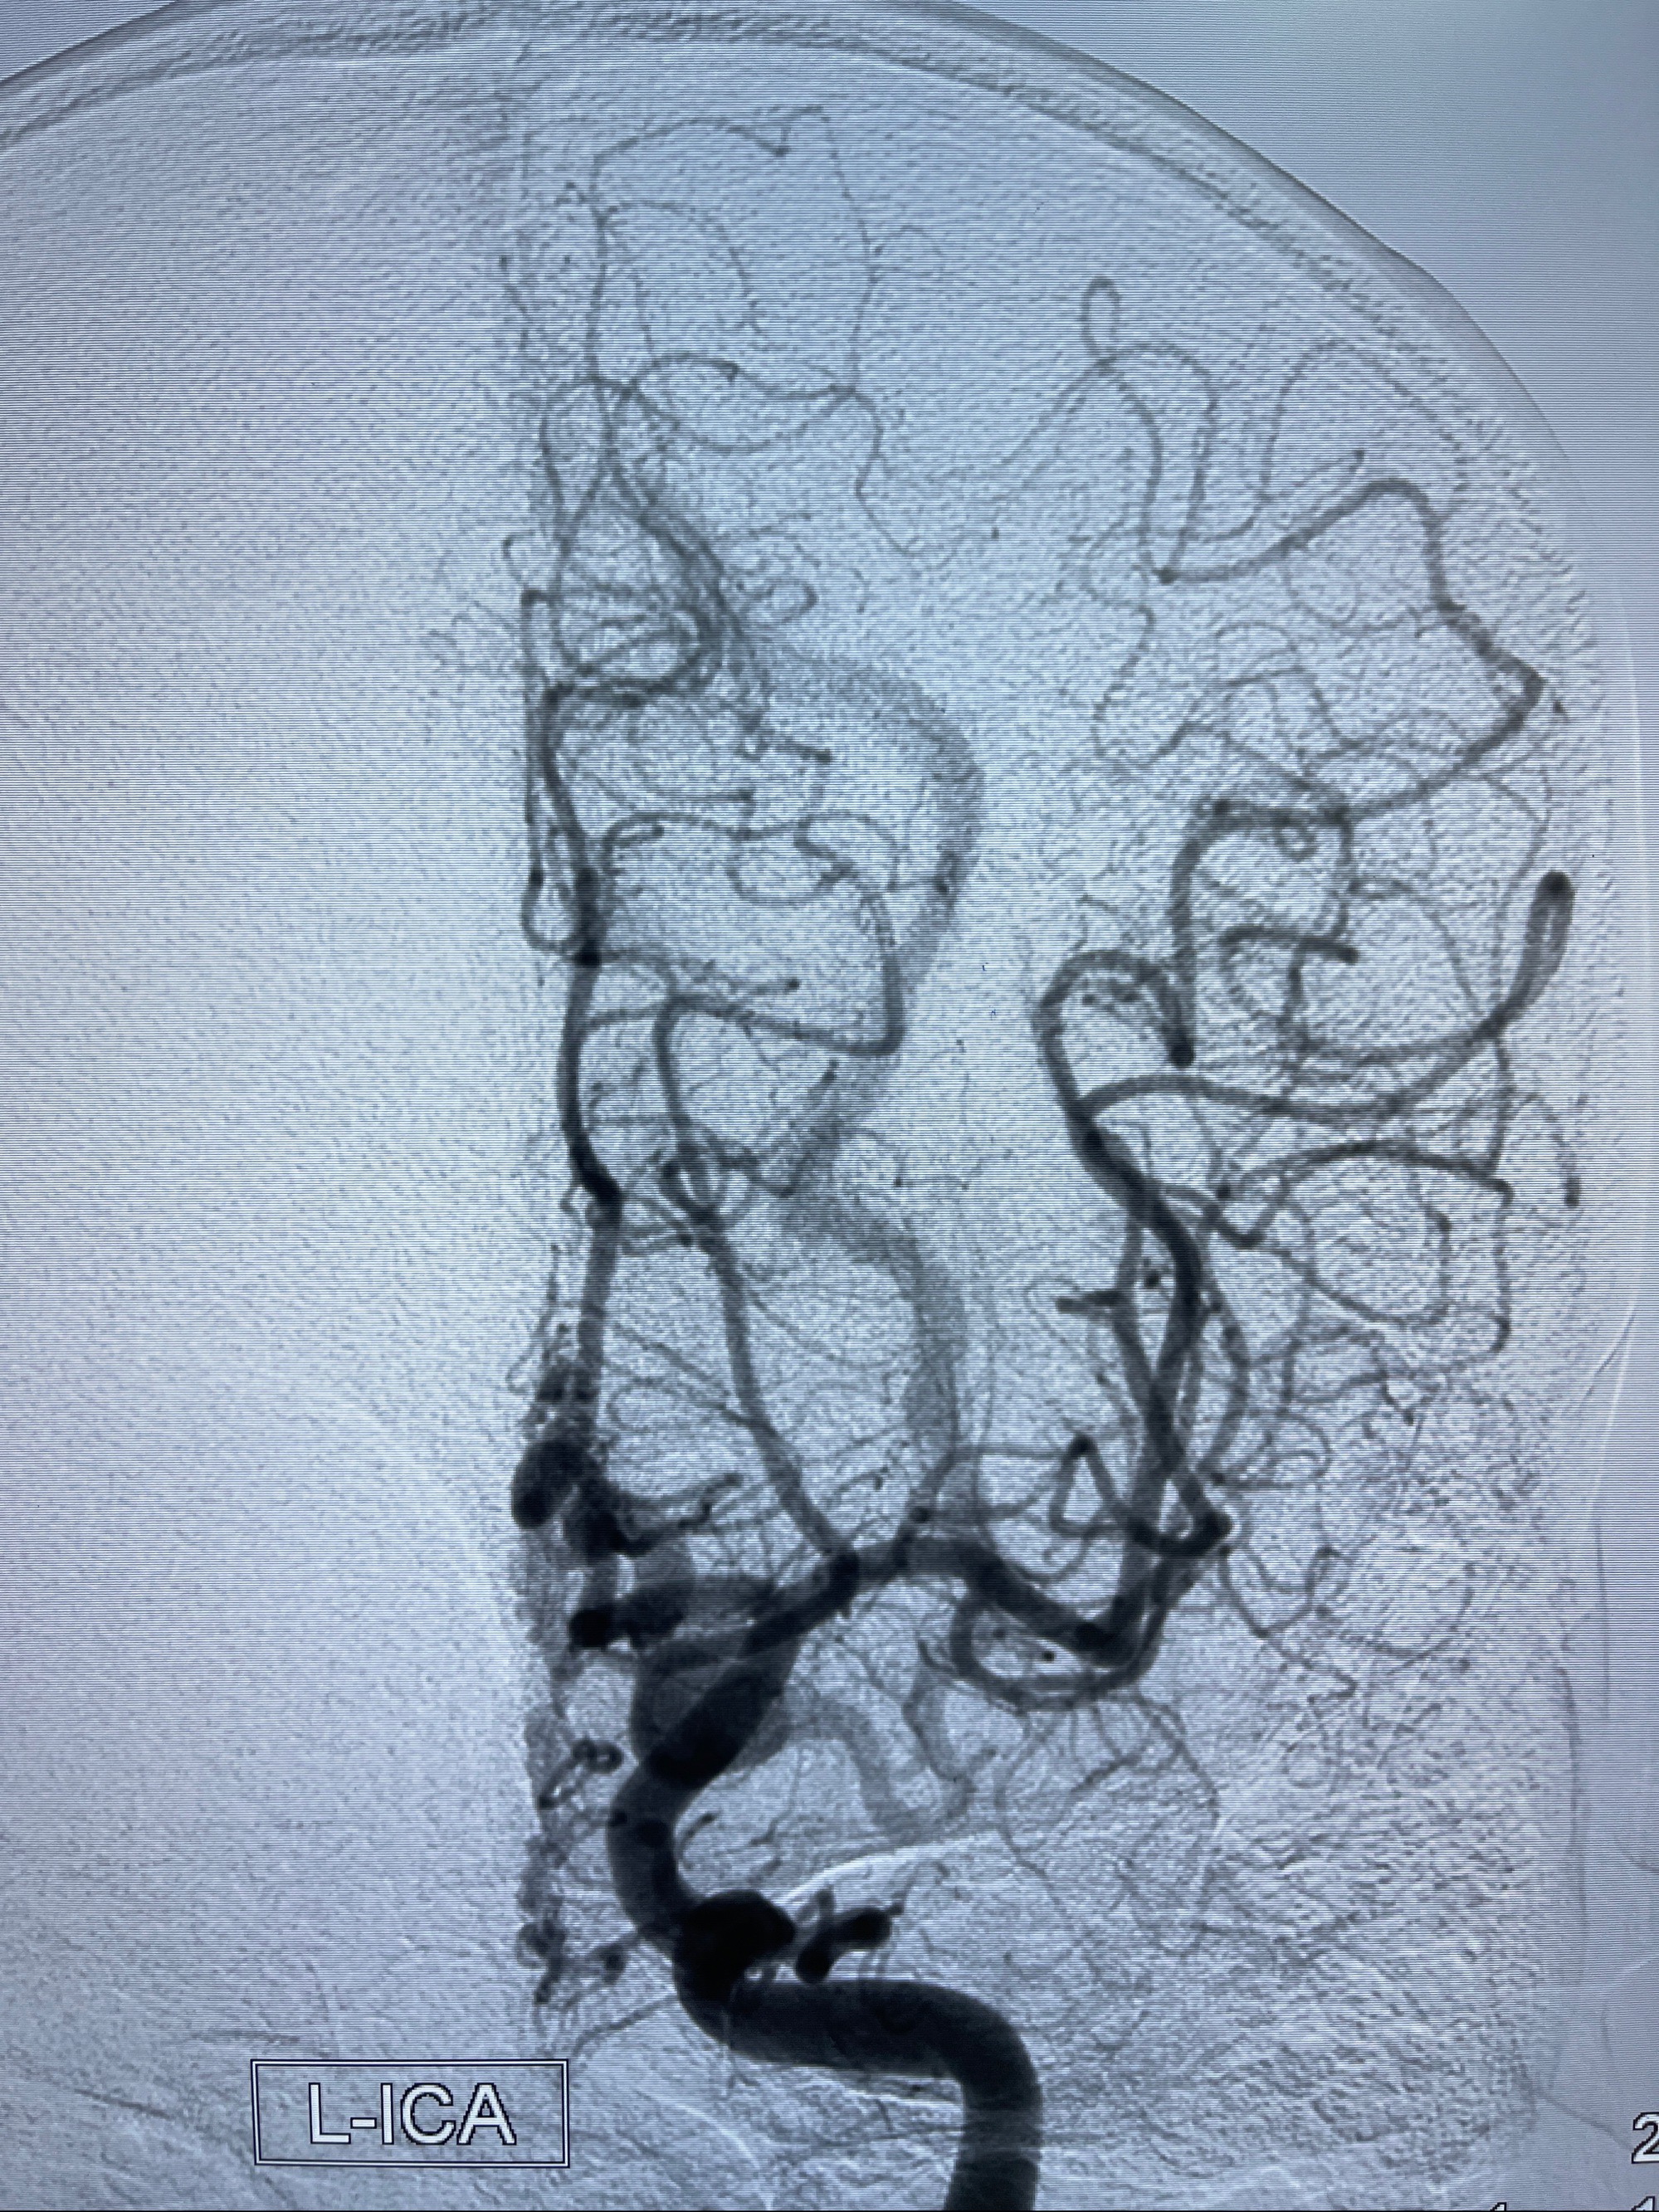

2023年8月21日]景德镇市第一人民医院脑血管造影检查,提示:主动脉弓、双侧颈总动脉、锁骨下动脉造影未见异常,左侧大脑前动脉静脉瘘。

2023-09-13全脑血管造影:前颅底硬脑膜动静脉瘘,供血动脉为双侧胼周动脉、眼动脉脑膜支,静脉向上矢状窦方向引流

- 介入干预:静脉途径栓塞or动脉途径填塞?